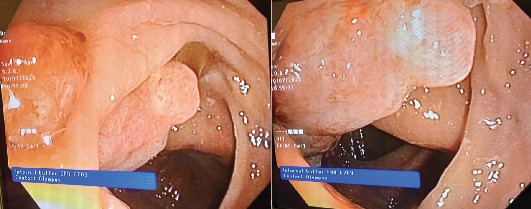

多发原发恶性肿瘤(MPMNs)是指同一个体出现两个或多个不同的肿瘤。同时发生的乳腺癌和结肠癌并不常见,由于缺乏标准化的指南,这给管理带来了挑战。我们报告一位73岁的女性右乳肿块,随后被诊断为2级浸润性导管癌。CT偶然发现右结肠壁增厚,结肠镜活检证实为中分化浸润性腺癌。在新辅助化疗后,她同时接受了根治性乳房切除术、腋窝淋巴结清扫术和右半结肠切除术。术后恢复顺利。辅助放化疗是根据多学科小组(MDT)建议进行的。同步乳腺癌和结肠癌对诊断和治疗计划提出了独特的挑战。MDT合作对于这些复杂病例的个性化治疗策略和优化结果至关重要。

Multiple primary malignant neoplasms (MPMNs) are defined as two or more distinct tumors in the same individual. Synchronous breast and colon cancers are infrequent and present management challenges due to the lack of standardized guidelines. We report a 73-year-old woman presenting with a right breast mass, subsequently diagnosed as Grade 2 invasive ductal carcinoma. Staging CT incidentally revealed right colon wall thickening, and colonoscopy with biopsy confirmed moderately differentiated invasive adenocarcinoma. Following neoadjuvant chemotherapy, she underwent simultaneous radical mastectomy with axillary lymph node dissection and right hemicolectomy. Postoperative recovery was uneventful. Adjuvant chemoradiation was administered per multidisciplinary team (MDT) recommendation. Synchronous breast and colon cancers pose unique diagnostic and treatment planning challenges. MDT collaboration is crucial for personalized treatment strategies and optimized outcomes in these complex cases.